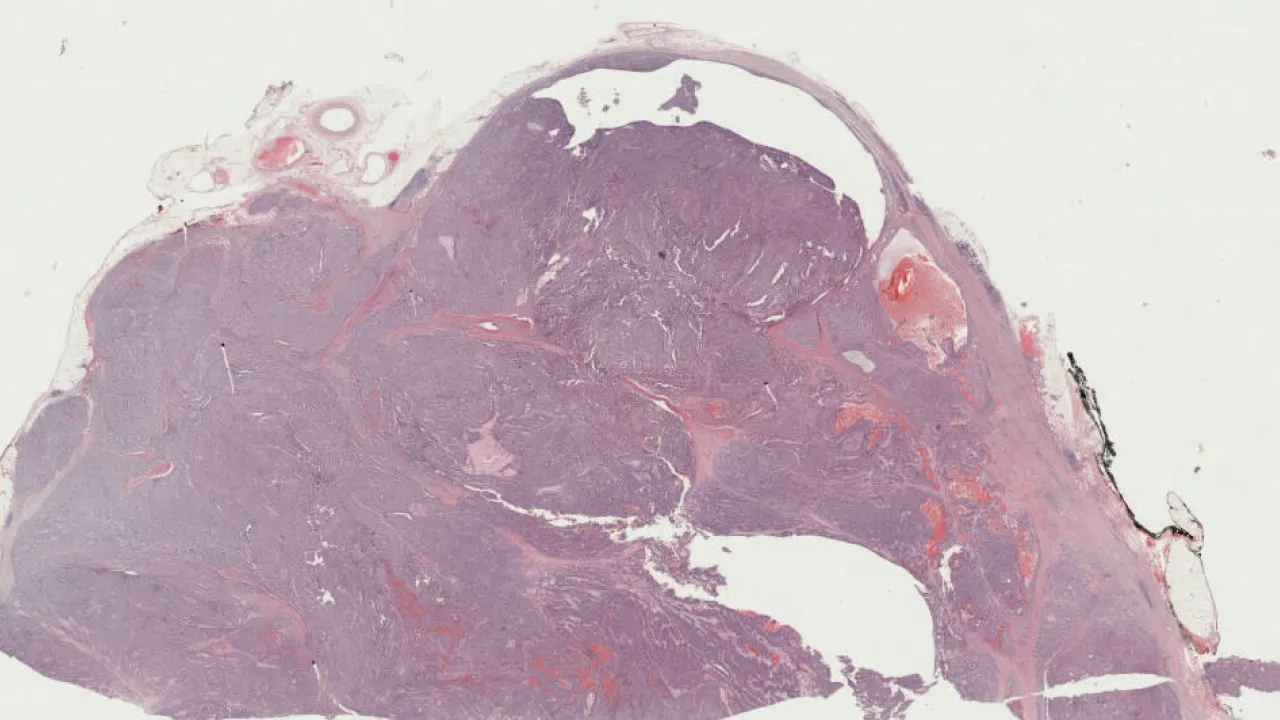

Pancreas, Intraductal papillary mucinous neoplasm (IPMN, non-invasive)